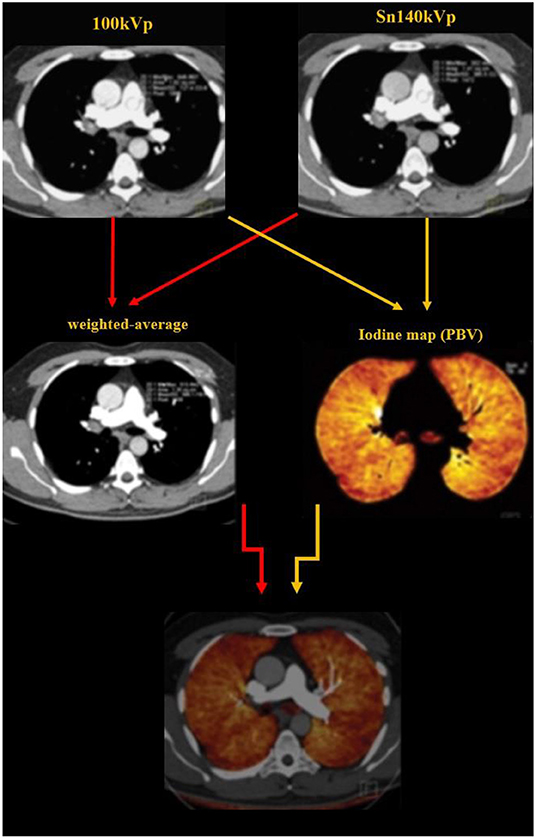

Image Reconstruction and Analysis

Typical image reconstruction was performed as three sets of images: 140-kV images, 100-kV images, and weighted-average images (with 60% and 40% weighting from Sn 100 kVp and Sn 140 kVp image series, respectively) with a specific medium convolution kernel (D31) at a 2.0-mm slice thickness and a 1.0-mm increment (Figure 2).

Figure 2. Image reconstruction was performed as three sets of images: 140-kV images, 100-kV images, and weighted-average images (with 60% and 40% weighting from Sn 100 kVp and Sn 140 kVp image series, respectively). The dual energy algorithm measures the attenuation in each voxel and uses the known standard attenuation ranges for the three major components of the lung parenchyma including the air, soft tissue and iodine, to calculate the relative contribution of each component to the voxel attenuation. The iodine distribution maps are subsequently created by the software.

Dual energy analyses were performed using the postprocessing software (Syngo MultiModality; Siemens Healthcare) with the “dual energy algorithm.” In this algorithm, the attenuation in each voxel is measure; using the known standard attenuation ranges for the three major components of the lung parenchyma including the air, soft tissue and iodine, the contribution of each component to the voxel attenuation is calculated. PBV maps were created from the images (Figures 2, 3) and whole lung enhancement (WLE) values were obtained. To measure the MPA enhancement, a region of interest circle of 10 mm2 was manually placed in the center of the arterial lumen on axial images, 1 cm before bifurcation. After normalizing the WLE based on MPA contrast enhancement, the PBV percentage (PBV) was automatically calculated by the software as an actual indicator of the total iodine distributed in the lung parenchyma relative to the iodine concentration in the MPA.